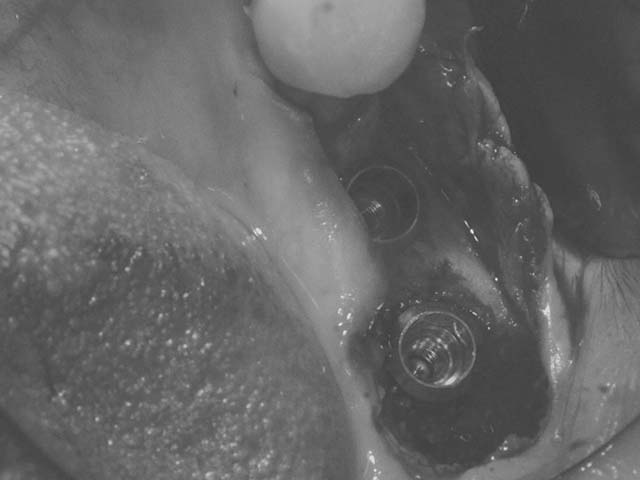

牙橋嚴重蛀牙,即拔即種,避免二次傷口 首頁 案例分享 人工植牙 牙橋嚴重蛀牙,即拔即種,避免二次傷口 多年前製作之牙橋,因為二度齲齒,導致支台齒蛀蝕,而需重新製作 牙橋支臺齒嚴重蛀牙 STEP1.拔除殘根並植入兩根植牙 STEP2.骨粉填補缺損骨頭缺陷 STEP3.三個月後,準備製作正式假牙 STEP4.正式假牙完成